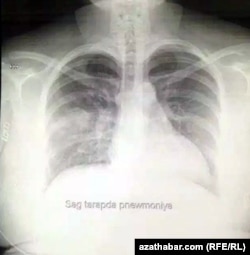

Также редакция Радио Азатлык получила рентгеновские снимки пациентов, заразившихся COVID-19.